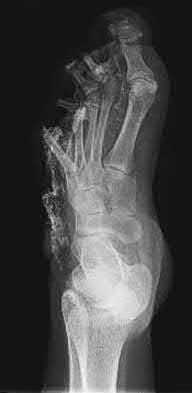

1. # A 32-year-old male sustains the injury shown in Figure A and undergoes treatment as shown in Figure B. Following placement of this implant, what is the best technique to confirm it is not too proud proximally?

1. Lateral radiograph of the knee

The safe zone for tibial nail placement as seen on radiographs is just medial to the lateral tibial spine on the anteroposterior radiograph and immediately adjacent and anterior to the articular surface as visualized on the lateral radiograph.

Tornetta et al specifically located the safe zone for nail entry in a study using fresh frozen cadaver knees. The authors found that the safe zone for nail placement is located 9.1+/-5 millimeters lateral to the midline of the plateau and three millimeters lateral to the center of the tibial tubercle. The width of the safe zone averaged 22.9 millimeters and was as narrow as 12.6 millimeters.

The starting point of the of the nail can be best viewed on the lateral knee radiograph, an example of which is shown in Illustration A. Illustration B shows the "sweet spot" for nail insertion as defined by Tornetta.